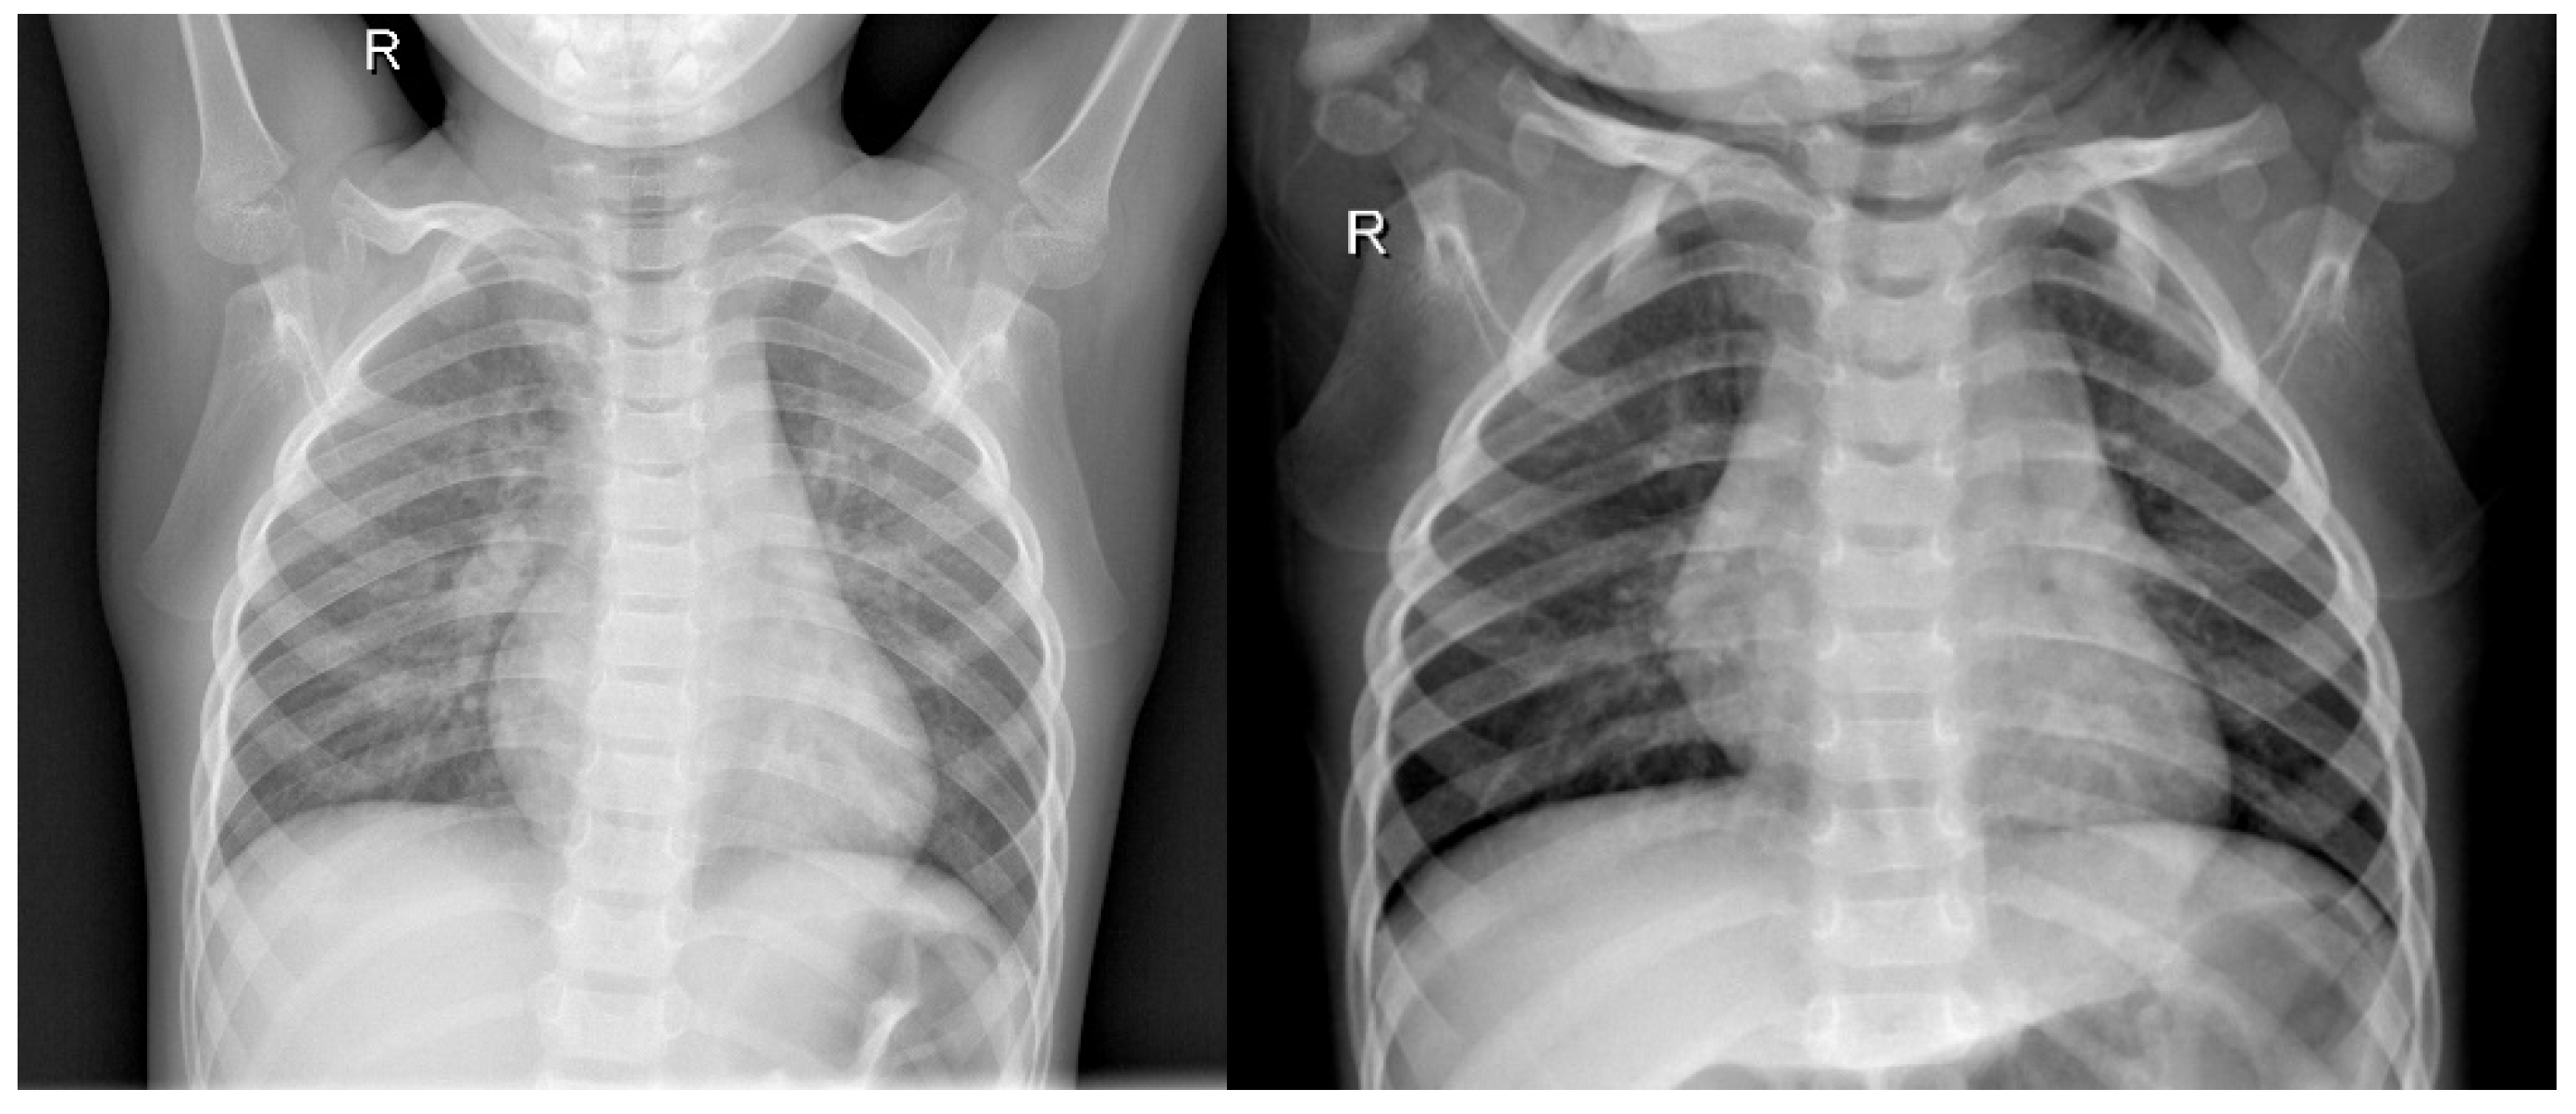

To obtain deep learning models with more generalization ability, the images of the original dataset need to be fairly pre-processed. Based on the center of each image, I cropped the original images to images of size 127 × 384—the smallest size in the dataset. All cropped images corresponding to the original images constituted the cropped dataset. In the following experiments, for the sake of conciseness and convenience, I refer to the cropped dataset as the original dataset (O) when there is no possibility of confusion. Figure 7 shows cropped images corresponding to those in Figure 5, and Figure 8 shows those corresponding to Figure 6.

It is obvious that the cropped images focus more on the lung part, and not the other peripheral parts, which generally contains other contents irrelevant to pneumonia. It can be expected that deep learning models trained using the cropped dataset will be more accurate than the original dataset.

The Hurst exponent images corresponding to the cropped images in Figure 7 and Figure 8 are shown in Figure 9 and Figure 10; the second partial derivative images corresponding to the cropped images in Figure 7 and Figure 8 are shown in Figure 11 and Figure 12; and the normalized average information content images corresponding to the cropped images in Figure 7 and Figure 8 are shown in Figure 13 and Figure 14, respectively.